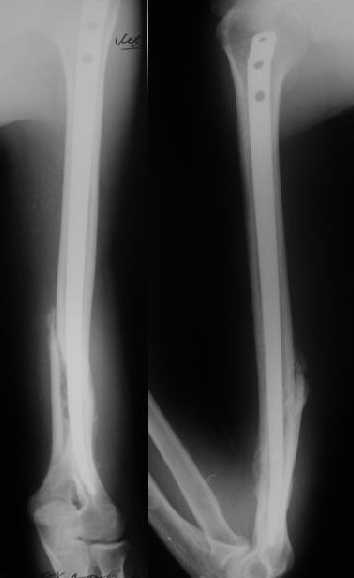

Снимки до, через 1 и 2 мес. после синтеза.